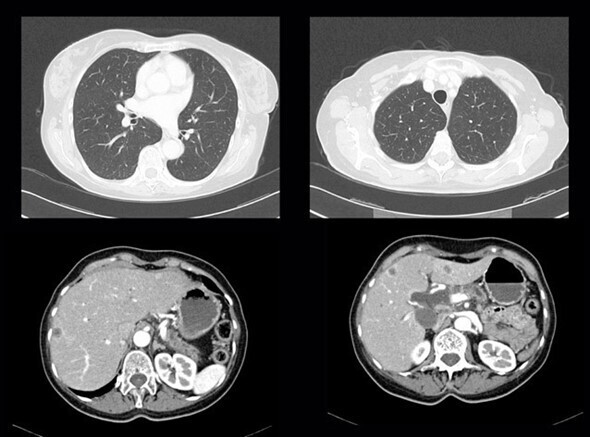

Vous recevez les résultats du scanner demandé (ci-dessous) ; les coupes sont représentatives et suffisent à conclure pour les organes explorés.

Question 9 - Sur cet examen, vous notez (une ou plusieurs réponses exactes) :

Le parenchyme pulmonaire est normal, on distingue uniquement les structures bronchovasculaires habituelles. En revanche on note des lésions hypodenses avec une prise de contraste périphérique hépatiques (flèches rouges) évoquant des lésions secondaires. Le reste du scanner est normal, la rate est visible (flèche bleue).

Le compte rendu du scanner confirme la présence de lésions secondaires hépatiques.